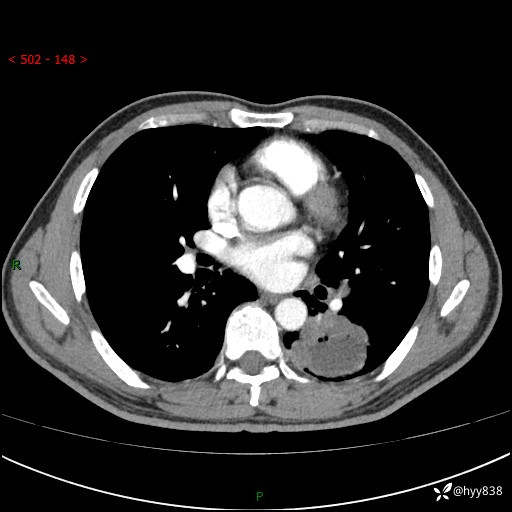

胸部CT平扫

增强